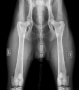

TEST ADN Myélopathie dégénérative : N/N (sain) TAN HD AA ED 00